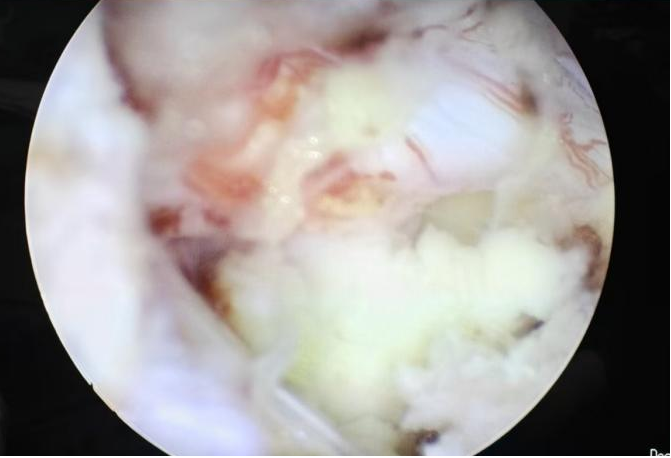

50歲的游先生因長期勞損,飽受腰痛與下肢放射痛折磨,保守治療無效,又因顧慮傳統(tǒng)手術創(chuàng)傷大、需植入螺釘而遲遲未決。我院脊柱團隊為其施行UBE下單側(cè)入路雙側(cè)減壓+椎間盤摘除+神經(jīng)根松解術,手術僅耗時50分鐘,術后24小時即可下床,3天出院,1個月后順利重返工作崗位。 內(nèi)鏡下減壓后影像 術后切口 病例二:高齡多病患者的“安全之選” 76歲的徐老先生患有嚴重腰椎管狹窄伴滑脫,合并高血壓、糖尿病,手術風險極高。經(jīng)多學科協(xié)作,團隊采用UBE技術為其完成減壓、復位、融合與內(nèi)固定,術中出血僅30毫升,無并發(fā)癥發(fā)生。術后第3天,老人已能下地行走,一周出院,家屬特贈錦旗致謝。 內(nèi)鏡下置入融合器 術后切口 術后DR片見滑脫已復位 病例三:復雜結(jié)核感染患者的“精準施治” 72歲的劉奶奶曾因椎體骨折接受骨水泥手術,后確診腰椎結(jié)核伴椎管內(nèi)膿腫,且體質(zhì)虛弱、伴有低氧血癥與貧血。團隊果斷采用UBE行椎管減壓+膿腫清除+骨水泥取出術,以微小切口解決重大隱患,術后患者疼痛顯著緩解,恢復良好。 術中取出椎管內(nèi)干酪樣膿腫 術中取出的骨水泥